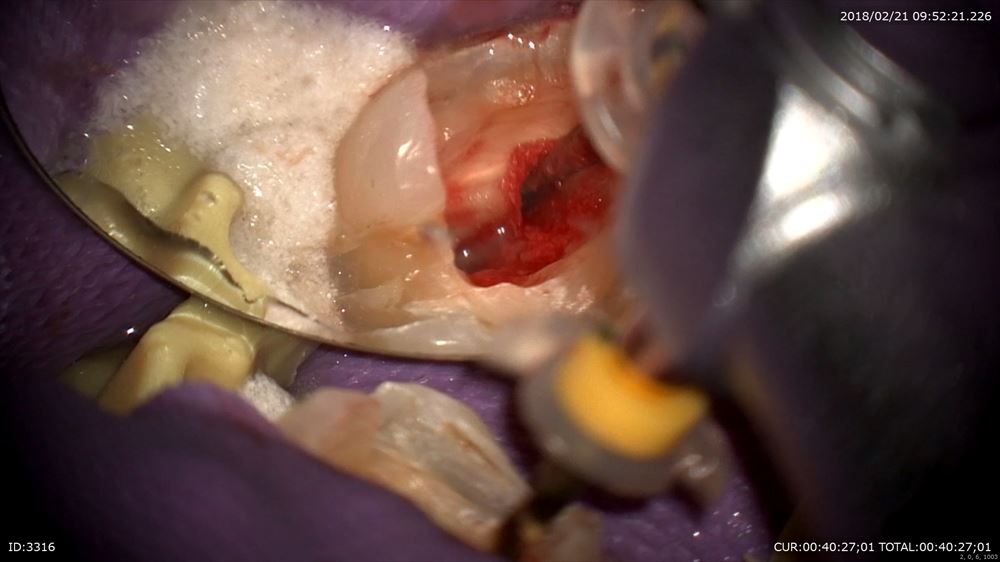

金属を外すと

神経が腫れていました

無痛で行います。

4根見つけて

綺麗になりました。